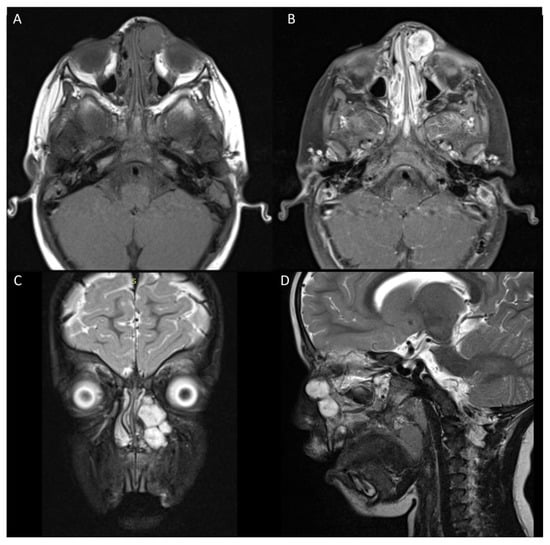

3.1. Case 1

3.2. Case 2